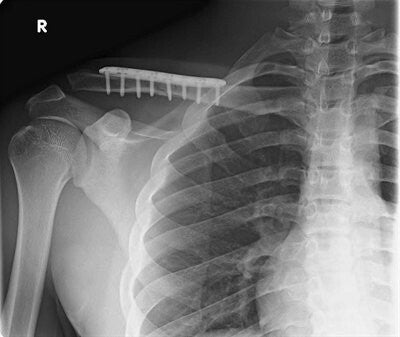

Bij een operatief herstel van een sleutelbeenbreuk zal er een insnede gemaakt worden over het sleutelbeen en vervolgens zal de breuk terug op zijn plaats gezet worden. Nadien wordt de breuk gestabiliseerd door middel van een plaat en schroeven. Deze houden de breuk op zijn plaats zodat die kan genezen.